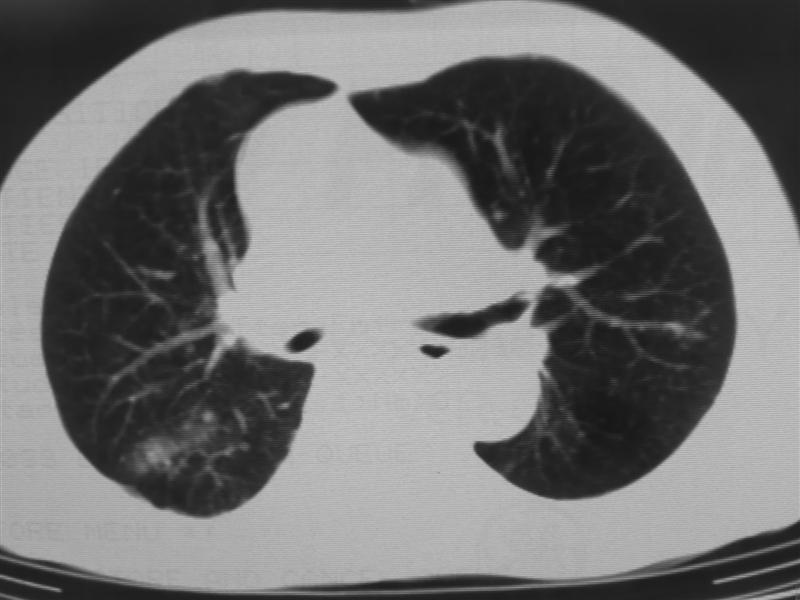

右下肺周围型肺癌伴双肺右侧叶间 胸膜及右肺门淋巴结转移

肺癌肺内转移。

肺癌、肺及胸膜转移可能性大;tb不除外